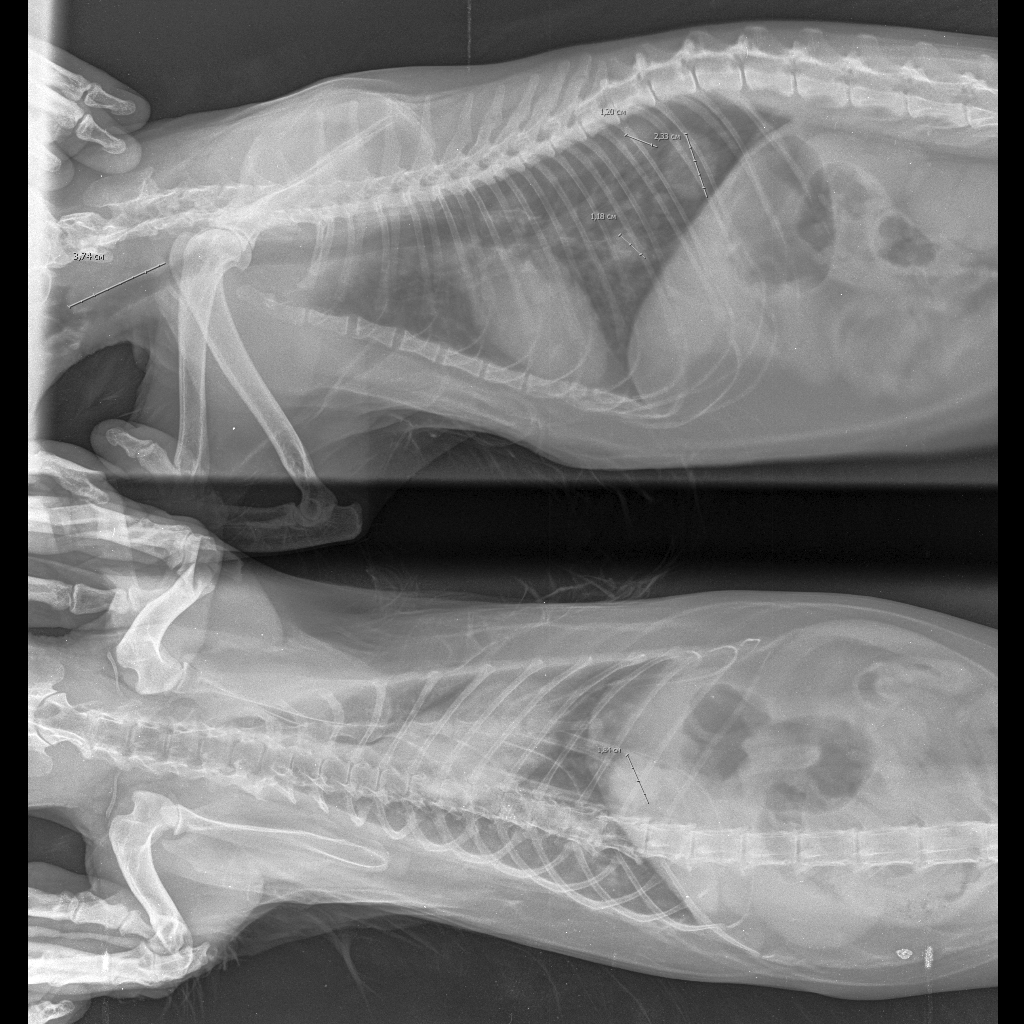

УЗИ показало множественное изменение внутренних органов, снижение перистальтики 12-перстной кишки, увеличение печени. Док говорит, это следствие наличия вирусов иммунодефицита и лейкоза.

Как минимум ищите нормальную вет клинику. Мы тоже намучились с кошкой из-за кашля, пока не нашли норм врачей. Сначал взяли анализы крови, потом сделали узи все органов, после рентген, по которому два независимых врача поставили диагноз бронхиальная астма. Назначенное лечение дало результаты уже через несколько дней.

- Рентген легких (Снимка нет, но по словам ветеринара - небольшое затемнение)